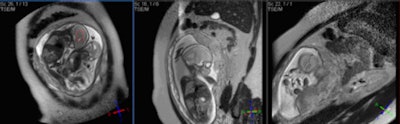

Fetal MR spectroscopy can assist with in utero measurements of fetal cerebral lactate concentrations. It may provide information on the adequacy of fetal oxygenation, and can help with decision-making on the optimal time of delivery. This figure shows fetal localizers used for spectroscopy measurements. Image courtesy of Janet De Wilde, PhD, and C. McComb."In the pre-examination questionnaire for determination of pregnancy, it is important to ask two questions: What was the first day of your last complete menstrual period? To the best of your knowledge, are you pregnant, or do you think you could be?" he said during last year's ECR refresher course on pregnancy.

In MRI, fast sequences are used to overcome image quality artifacts caused by fetal motion, and this can lead to the use of high-specification magnetic field gradients; the frequency range for the gradients is from 1 kHz to 10 kHz. The main concerns are the clinical effects of low-frequency EMF (electromagnetic fields)-induced currents and acoustic noise, but overall there is no indication the use of clinical MR procedures during pregnancy produces adverse effects, according to Janet De Wilde, PhD, executive manager of SINAPSE (Scottish Imaging Network: A Platform for Scientific Excellence) at the University of Edinburgh.

| Sagittal HASTE image used for planning further fetal images in other planes, taken at the Clinical Research Imaging Center, University of Edinburgh. Image courtesy of Janet De Wilde, PhD, and Dr. Scott Semple. |